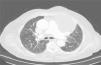

La paciente había ingresado en el servicio de Neumología por episodios repetidos en los últimos 2 años de infección respiratoria con presencia de sibilancias inspiratorias de predominio en hemitórax izquierdo. Se realizó una TAC de tórax, donde se objetivó una lesión quística de 10×9cm que ocasionaba atelectasia parcial del lóbulo superior izquierdo y compresión de estructuras mediastínicas (fig. 1). Se programó una punción de dicha lesión guiada por TAC, cuyo estudio citológico fue compatible con linfangioma quístico.